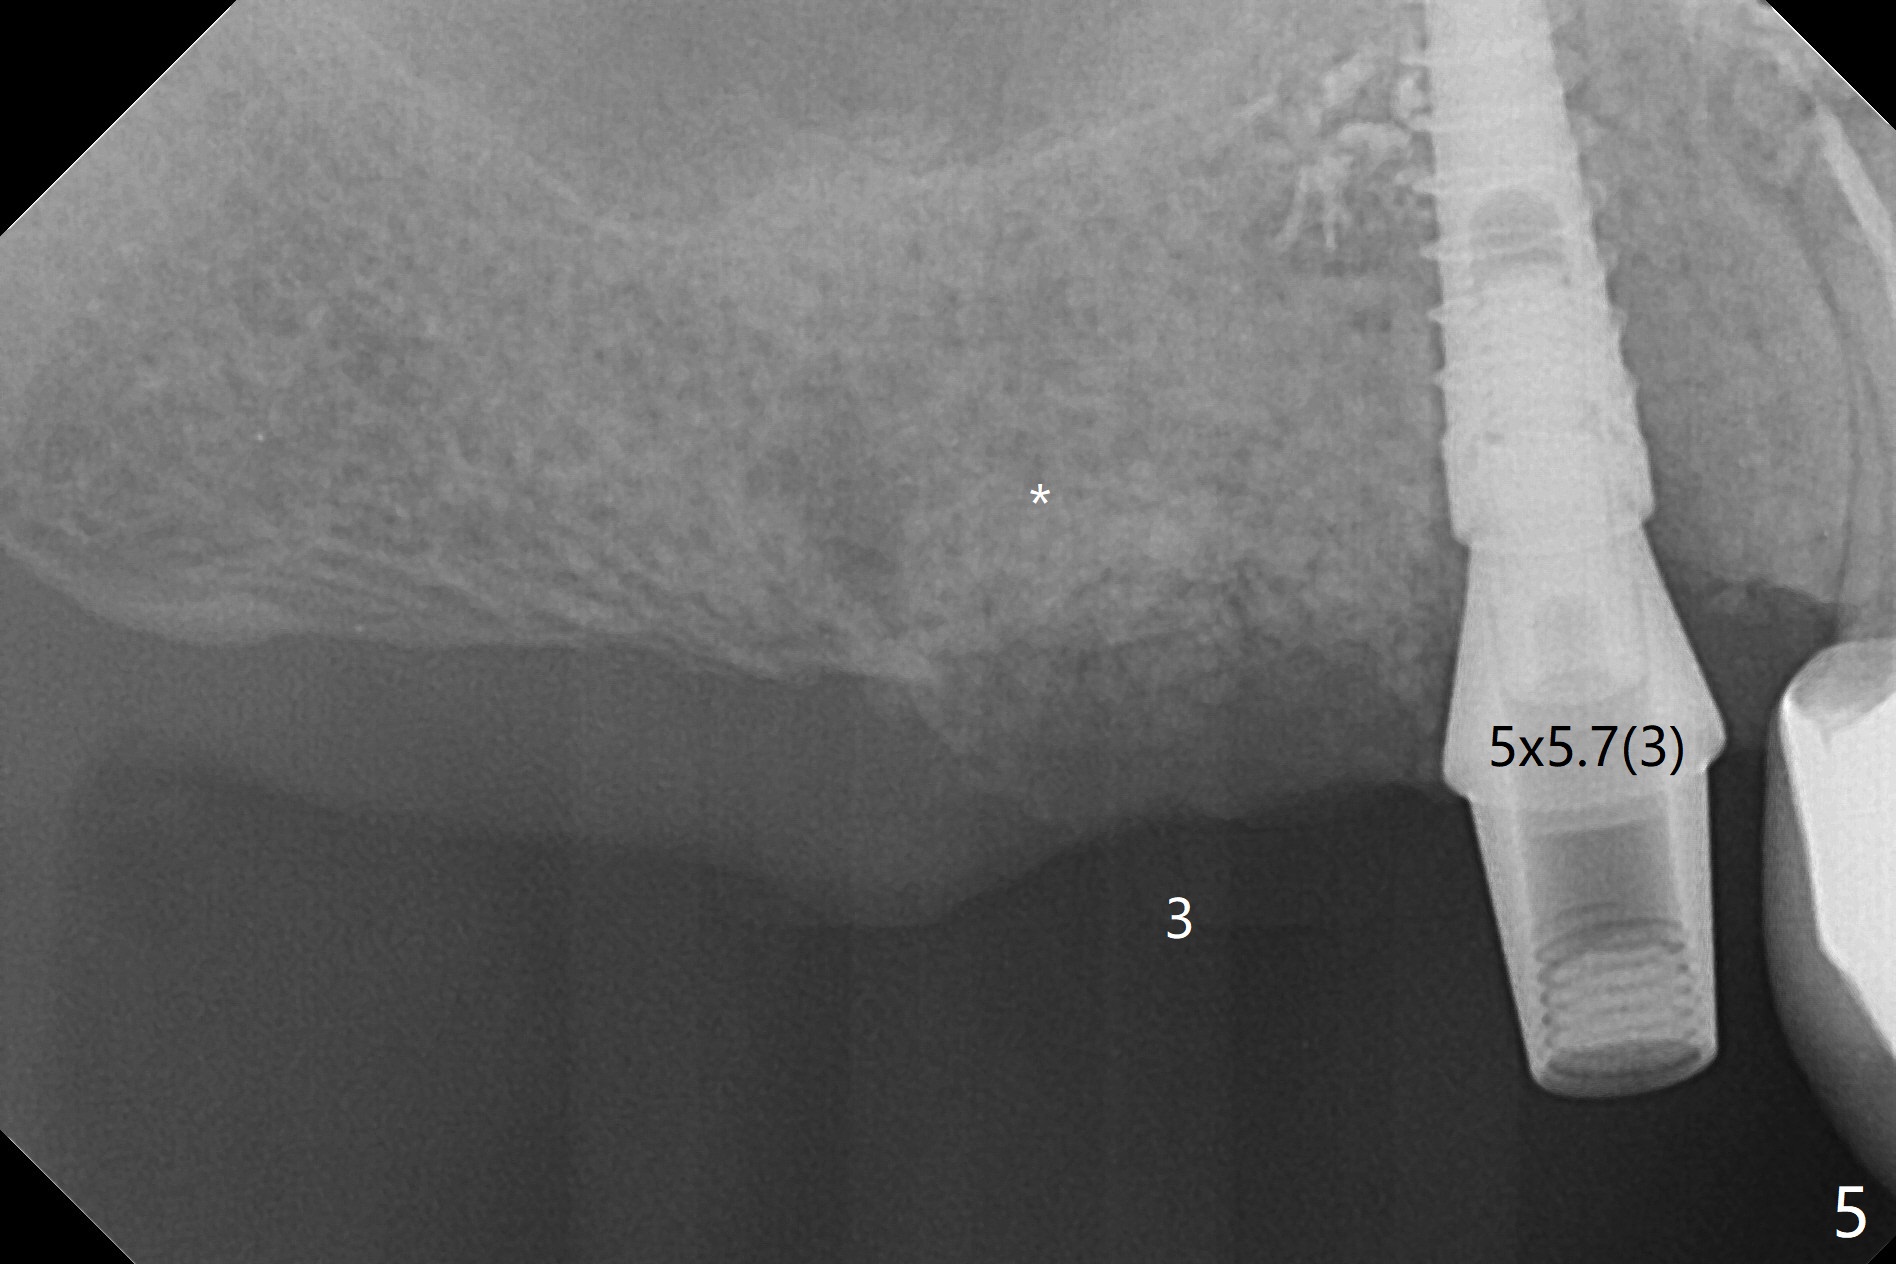

The patient returns for #4 extraction and immediate implant the 1st day clinic reopening after coronavirus lockdown. To reuse autogenous bone for #4 buccal gap closure, delayed implants are also placed at #13 and 14. It is much easier to determine the placement level of the immediate implant (open socket) with guide than that of the delayed ones (flapless) clinically. Immediate postop CT is taken for implant placement level confirmation (Fig.1-3). In fact the autogneous bone is too soft to be packed into #4 socket gaps. It has to be mixed with allograft to be packable. There is oozing when #14 healing abutment is placed. The hemorrhage is severe 4 days postop. The healing abutment is replaced by a healing screw. Hemostasis is achieved when the access is closed with GEM Cap and 4-0 Chromic gut suture. The patient will return for #3 extraction and socket preservation 1 month postop (Fig.4). To prevent postop hemorrhage, a cemented or temporary abutment will be placed at #4 before anesthesia, while .5 or 1.0 cc Augma bone will be placed at #3, covered with collagen plug and acrylic. In fact he cancels the appointment once because of symptom relief and will return 2 months postop. Sticky bone (Fig.5 *) and PRF is used at #3 for hemostasis, while a 5x5.7(3) mm pair (final) abutment is used to hold acrylic dressing in place. The latter remains in place with good oral hygiene 1 month postop (Fig.6 A: abutment). When the acrylic dressing is removed, the socket heals (Fig.7 K: the gingiva between the buccal and palatal sockets when the tooth was removed). The patient returns for impression 4.5 months postop. When the 5x5.7(3) mm abutment at #4 is reseated after cleaning, there is no horizontal gap between the abutment and implant in BW (Fig.8), while there is in PA (Fig.9). When a smaller abutment is seated (Fig.10), there appears to be a horizontal gap, whereas there is no vertical one. The situation is the same with #13 (Fig.11,12). The common denominator is 3.5 mm implant. With suspicion, BW is taken for the implant at #4 immediately before cementation (Fig.13). It appears that the abutment is most likely seated completely. There is no bone loss or screw loosening 4 months post cementation (Fig.14,15). One month later the patient agrees to have 3 lower implants to replace RPD.